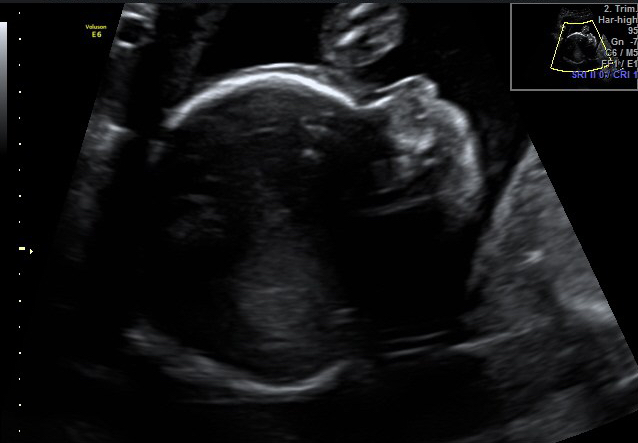

come una mamma aspetta quell’ecografia

Click dentro al pancione